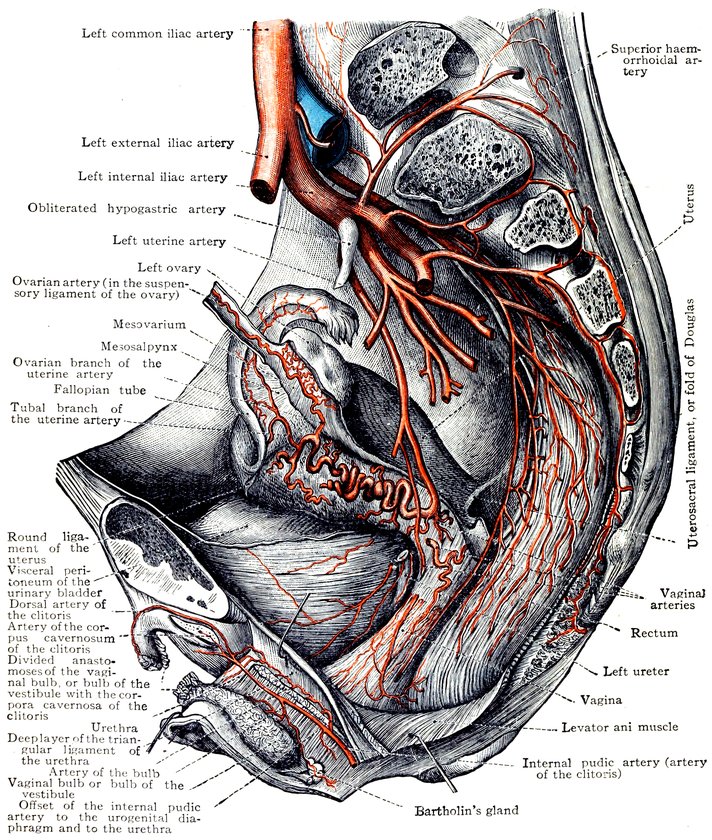

Fig. 4.—The distribution of the lateral sacral arteries, the superior haemorrhoidal or superior rectal artery, the uterine artery, the ovarian artery and the distal portion of the internal pudic artery. (From Toldt: Atlas of Human Anatomy.—Rebman Company, New York.)